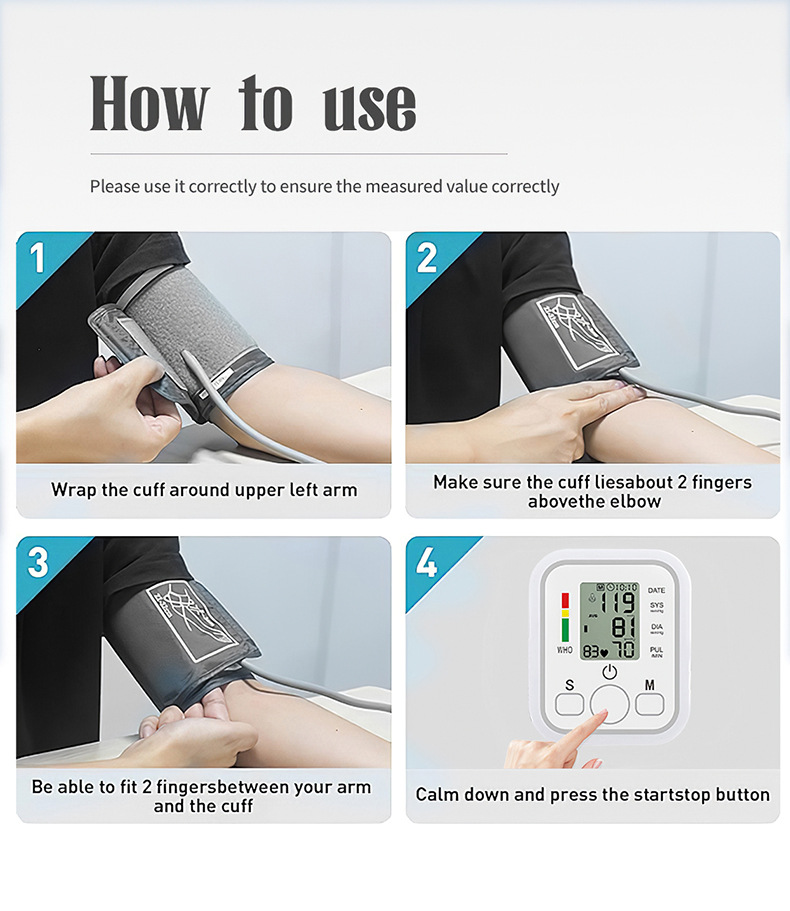

Product Image: